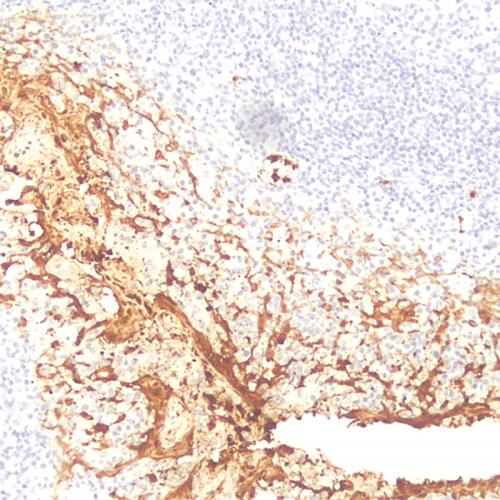

病理HE染色液主要用于顯示各種組織正常成分和病變的一般形態(tài)結(jié)構(gòu),進(jìn)行全面觀察。HE染色技術(shù)是病理解剖學(xué)、組織胚胎學(xué)、法醫(yī)學(xué)和生物學(xué)等領(lǐng)域最基本的技術(shù)操作,其在病理診斷、教學(xué)以及科研中廣泛應(yīng)用,具有重要價值。細(xì)胞中細(xì)胞核是由酸性物質(zhì)組成,它與堿性染料(蘇木素)的親和力較強(qiáng)。而細(xì)胞漿則相反,它含有堿性物質(zhì),與酸性物質(zhì)(伊紅)的親和力較大。因此,細(xì)胞或組織切片經(jīng)HE染色液染色后,細(xì)胞核被染成藍(lán)色,細(xì)胞漿、紅細(xì)胞、肌肉、結(jié)締組織、嗜伊紅顆粒等被染成不同程度的紅色或粉紅色,與藍(lán)色的細(xì)胞核形成鮮明的對比。